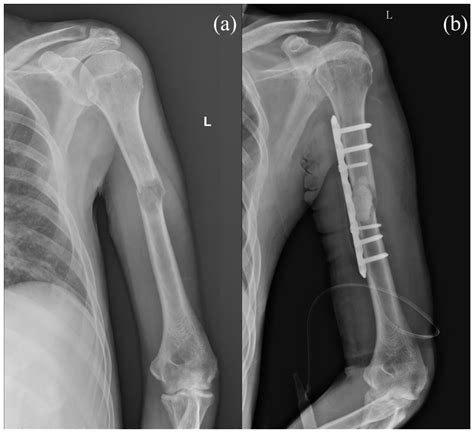

The journey through Open Fixation Surgery typically begins with comprehensive imaging, such as X-rays or CT scans, to map the fracture. Once the patient is under general or regional anesthesia, the surgeon makes an incision over the affected area to expose the bone. This "open" approach is what differentiates it from minimally invasive procedures, as it provides the surgeon with a clear view of the damage.

During the operation, the surgeon clears away any debris or blood clots and aligns the broken fragments. Once satisfied with the alignment, they secure the bone using internal fixation devices. These devices act as an internal scaffold, providing the structural integrity that the bone currently lacks. After the hardware is firmly in place, the incision is closed with sutures or staples, and the limb is often protected with a temporary cast or splint.

Reduction Direct visualization and manual realignment of bone fragments.

Fixation Placement of plates, screws, or intramedullary nails.